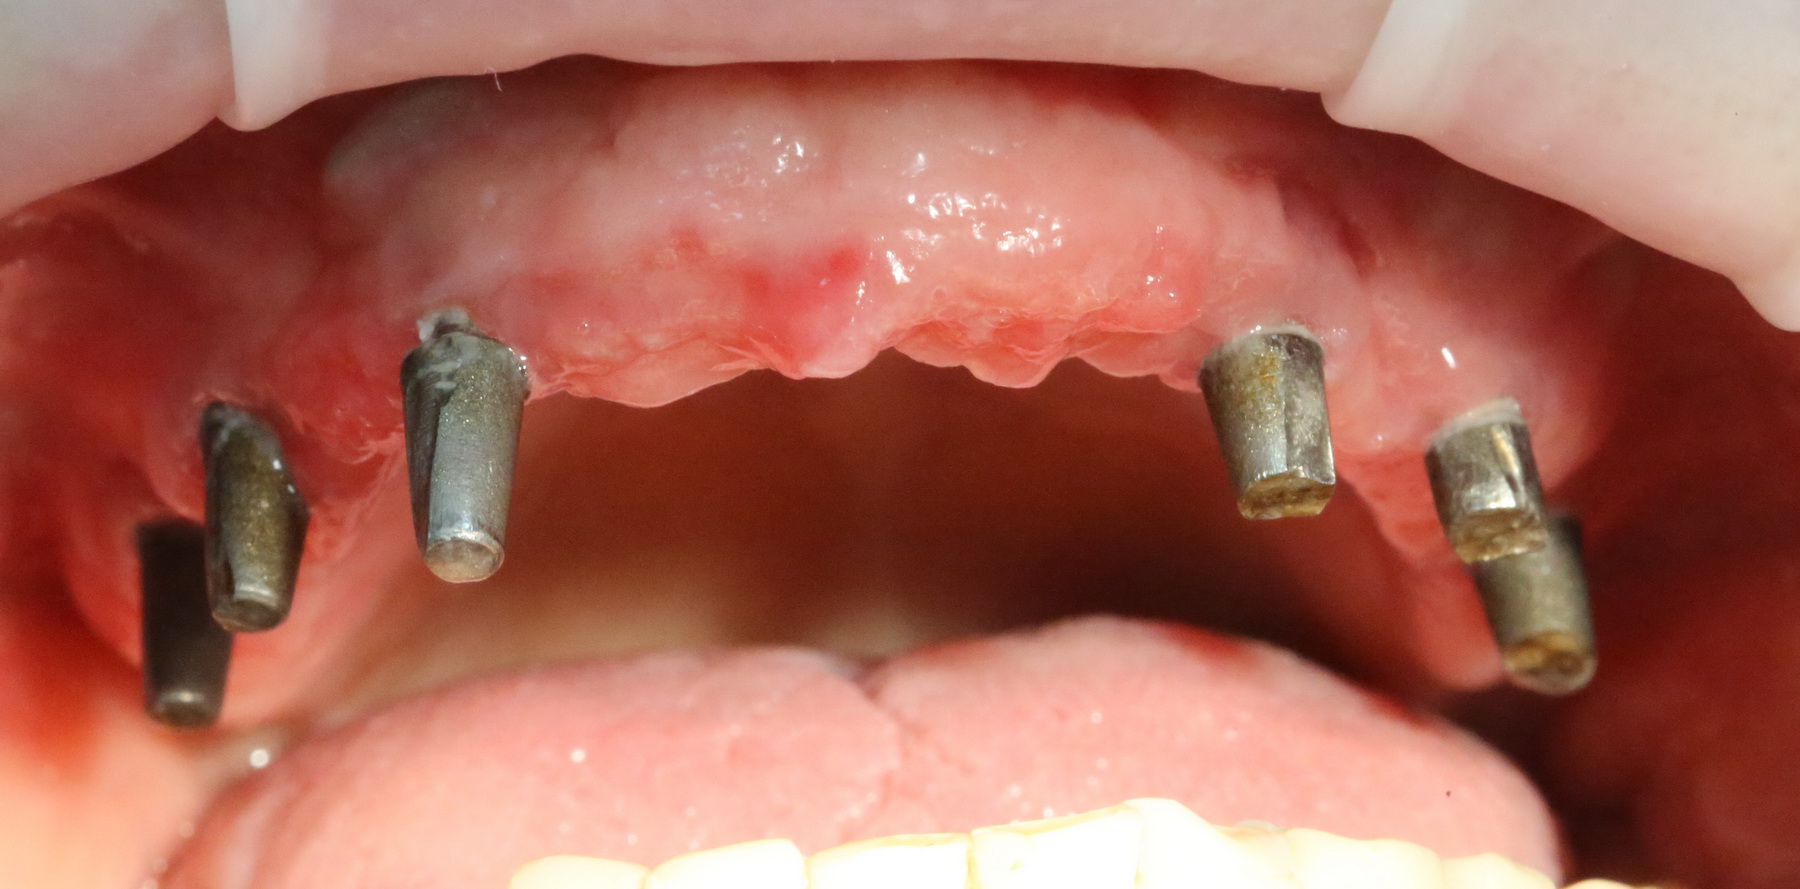

и, периодически, мне приходится видеть пациентов с базальными имплантами:

Как правило, вся работа с этими имплантами сводится к их удалению:

И вот, у этой пациентки все импланты, а их, ни много, ни мало, восемь штук, подвижны:

Мы вынуждены их удалить. И теперь представьте, как будет проходить такое удаление и с каким дефицитом костной ткани мы, в итоге столкнемся. Что вообще делать дальше? Девушка плачет.

Хотите на это посмотреть? Этого не покажут, рекламируя базальную имплантацию:

То есть, друзья, десны нет. За подобную работу в наших клиниках рвут диплом в клочья и выгоняют нафиг. Для базальной имплантации, такая ситуация — норма:

И теперь представьте, как за всем этим ухаживать? Как этим жевать, если учесть тот факт, что ножка импланта, торчащая из десны, легко гнется? И сколько такие импланты вообще прослужат, если учесть сложную гигиену и неудобную форму протеза в этом участке?

Жаль, но мы вынуждены эти базальные импланты удалить, проводить остеопластику и ставить другие, обычные винтовые импланты. И, к счастью, уже закончили эту работу, как нибудь расскажу вам о ней.